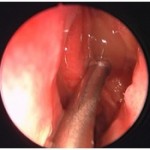

Figures 4a and 4b Pre- and Post-Rhinotopic Therapy: Chronic hyperplastic sinusitis in a patient prior to the topical treatment (left). The ethmoid and frontal mucosa is polypoid; the maxillary antrostomy is patent. Same patient after completion of the rhinotopic protocol (right). The sinus mucosa health has been restored.